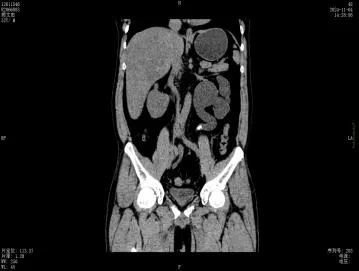

今年8月起,左腰部酸胀频繁不适,这才想起医生曾经的叮嘱,后找到深圳市罗湖区人民泌尿外科姜刚刚副主任医生门诊就诊,行CT检查发现整个左肾重度积水,而结石仍旧卡在输尿管内,最终只能无奈手术切除没有功能的左肾。

肾积水就像水管堵塞会导致水池溢水一样,结石堵塞了尿路,尿液排不出去就会回流,导致肾脏被越撑越大,这就是“肾积水”。长期的积水会像泡在水里一样,压迫并损坏肾脏的实质细胞,导致肾功能永久性丧失。